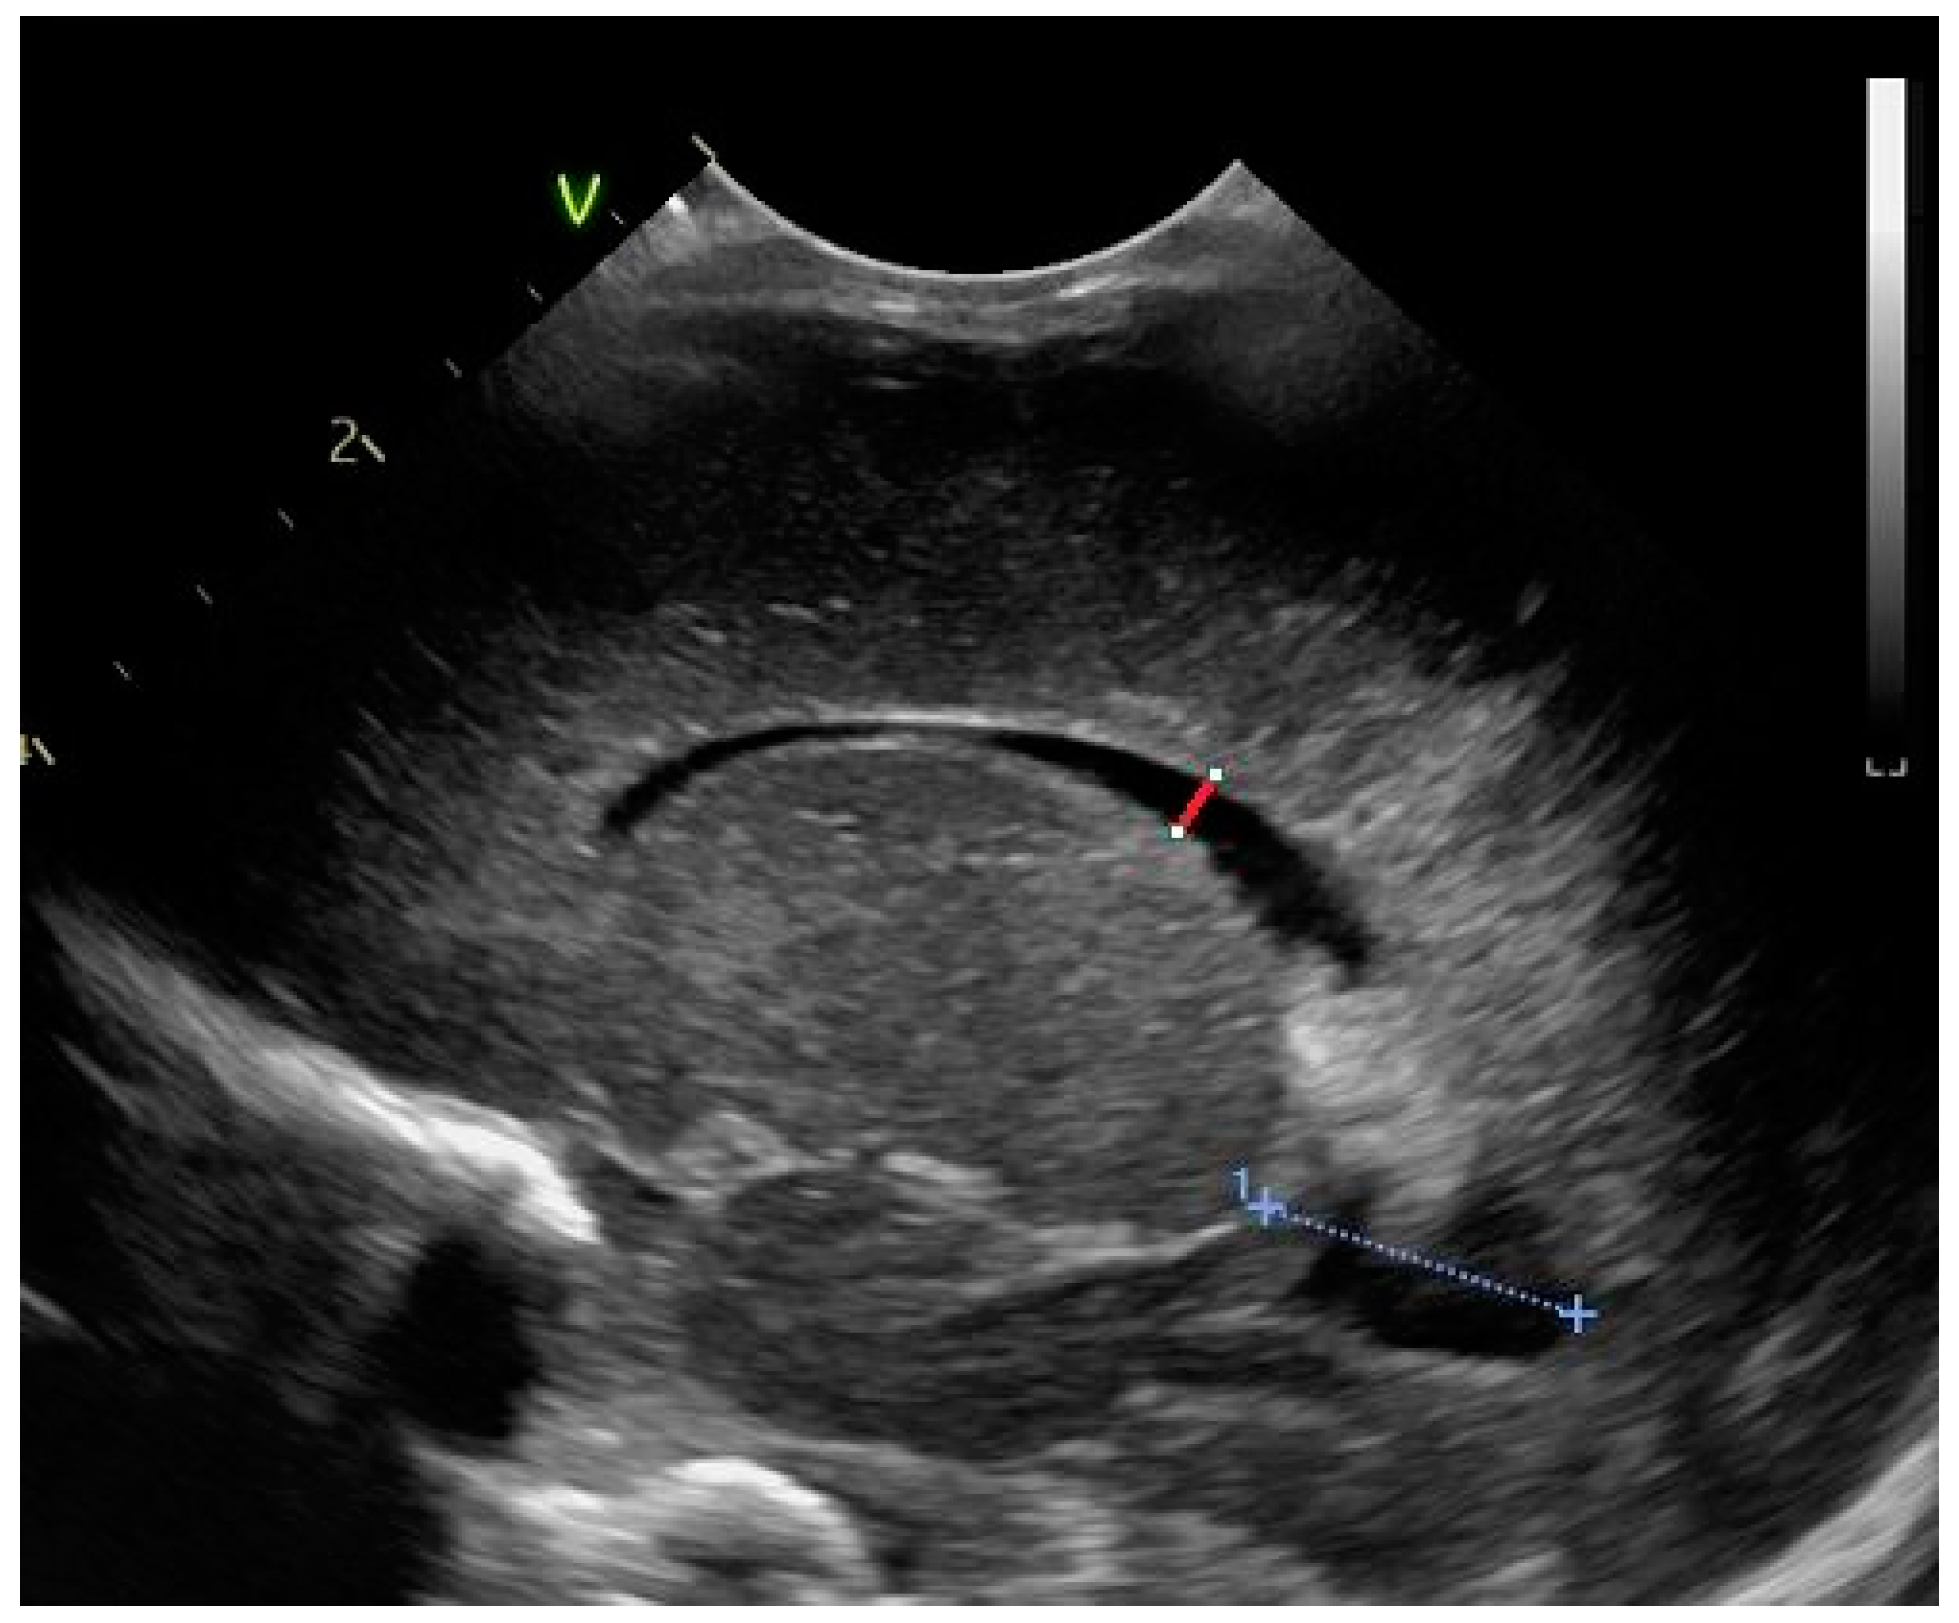

2.2. Head Ultrasound Measurements at TEA